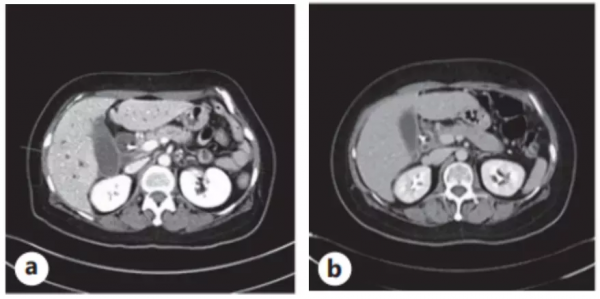

入院後化驗總膽紅素為 6.3 mg/dL,AST 190 IU/L,ALT 287 IU/L,ALP 441 IU/L,CA 19-9 8840 U/mL。增強CT檢查發現胰腺有直徑1.4 cm 的腫物,進一步的MRI發現了多處肝轉移。超聲內鏡活檢確診為胰腺導管腺癌伴多發肝轉移。

患者以吉西他濱聯合白蛋白結合型紫杉醇作為一線化療方案,兩個週期後,病情穩定,但四個週期後進行病情評估,疾病進展了。此時化驗,AST 22 IU/L,ALT 8 IU/L,ALP 59 IU/L,CA 19-9 8961 U/mL。

圖2. (a)脂質體伊立替康治療前,胰腺癌的原發灶和多發性肝轉移。(b)脂質體伊立替康五個月後,原發灶體積縮小,肝轉移消失